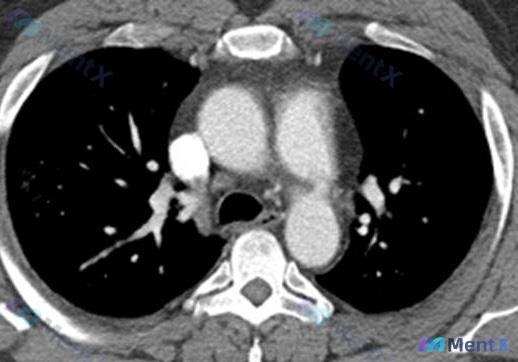

看到一个挺有意思的创伤病例,整理了一下资料和自己的思路,和大家分享讨论。 --- 病例基本情况 - 背景:摩托车碰撞事故(高能量减速伤机制) - 检查:胸部增强CTA(纵隔窗横断面) 影像原始观察(基于提供的描述) 1. 纵隔与气道:气管居中、通畅,纵隔结构位置正常 2. 心脏大血管:主动脉弓及降主...

整理到一个有点意思的病例,年轻女性,高能量机动车事故后,为了评估潜在的主动脉损伤做了增强心肌CT血管造影(胸部增强CTA)。 先给个初始背景:影像里主动脉弓走行是好的,没有明显的夹层、动脉瘤或造影剂外溢。但仔细看,可能有个被外伤背景掩盖的问题——而且不在主动脉上。 大家第一眼会先考虑什么?如果主动脉...